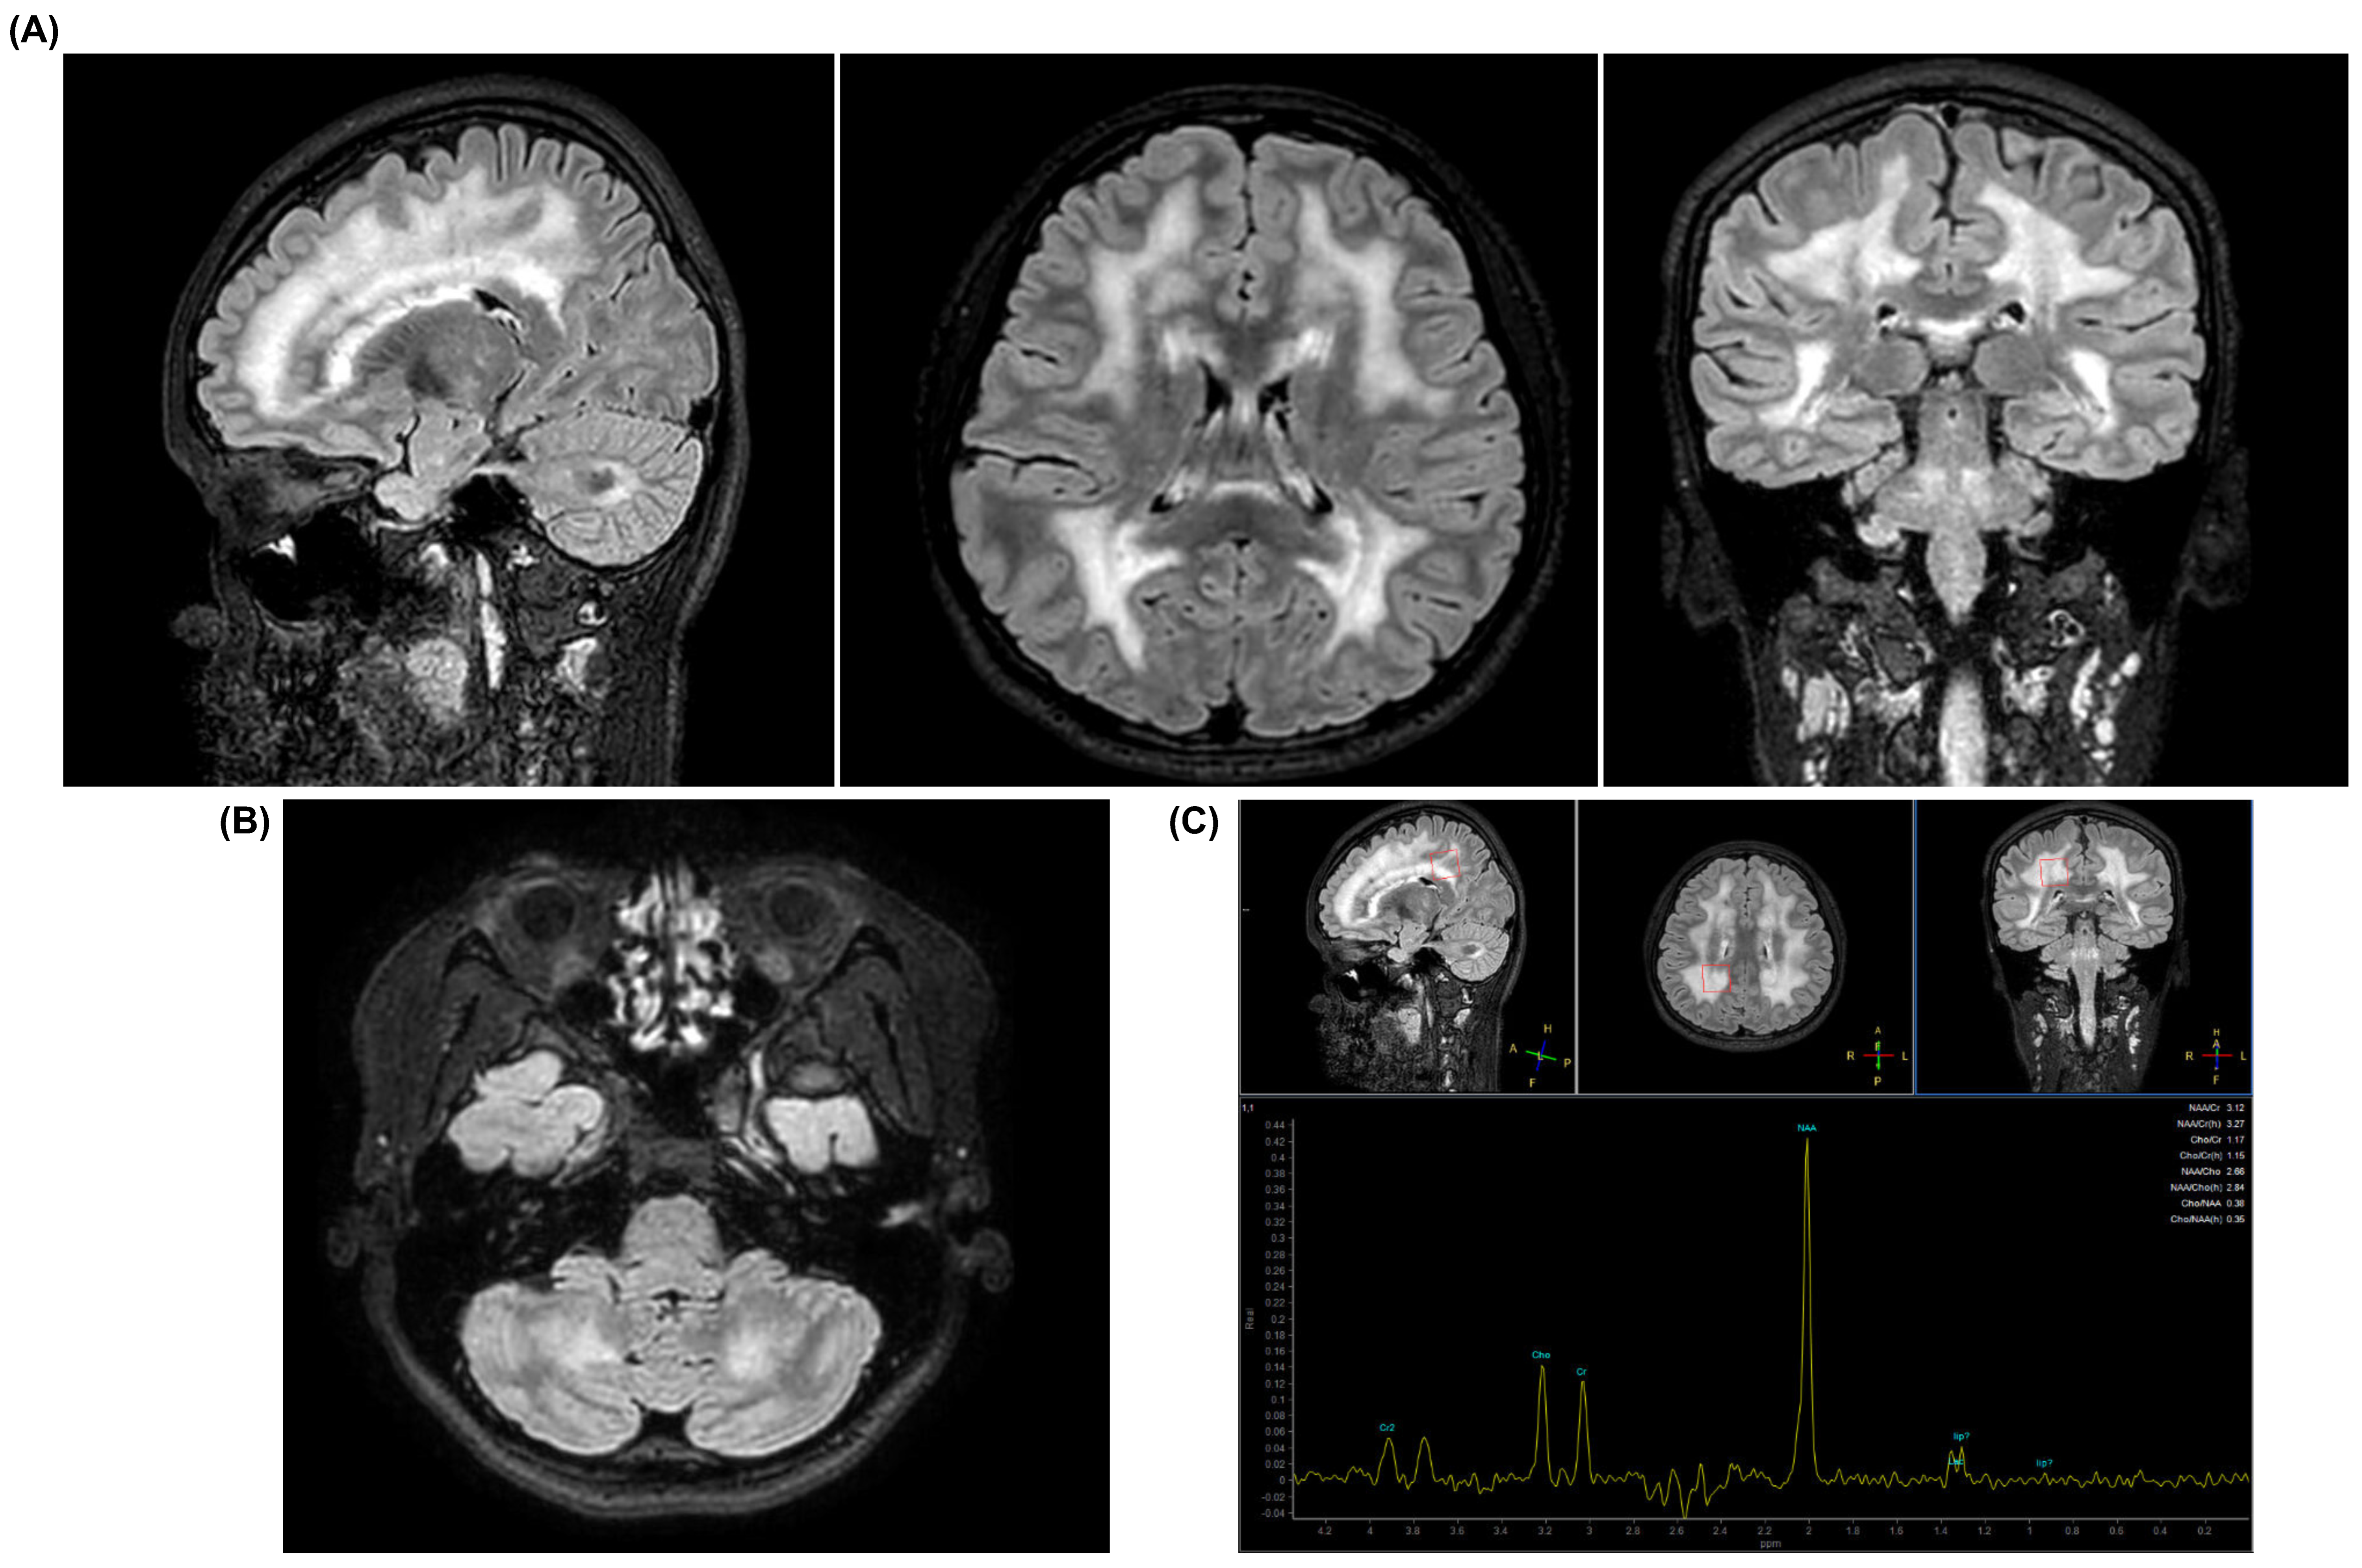

| Neurological signs | Yes, motor peripheral neuropathy, leukoencephalopathy | Yes, demyelinating sensory motor peripheral neuropathy, electromyogram abnormalities, leukoencephalopathy, ptosis, muscular atrophy | Yes, leukoencephalopathy | Yes, demyelinating sensory motor peripheral neuropathy, electromyogram abnormalities, leukoencephalopathy |